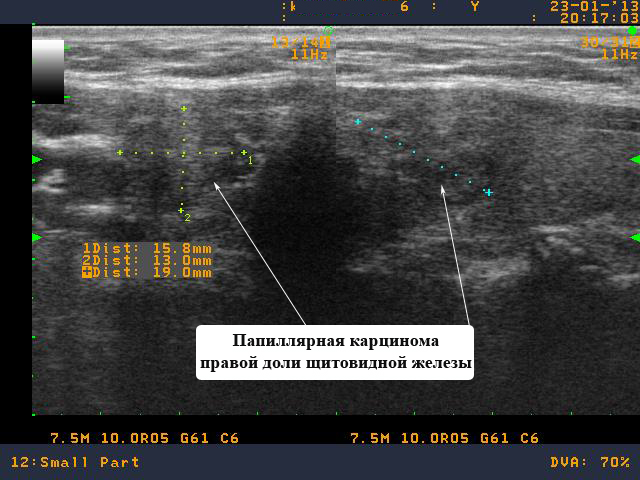

В данном клиническом случае представлена пациента К. 43 лет из города Луга (Ленинградская область). Пациентка обратилась на очную консультацию, во время которой, было выполнено УЗИ щитовидной железы и обнаружен узел в правой доле щитовидной железы размерами 15 на 13 на 19 мм.

Мною было предложено выполнить тонкоигольную аспирационную биопсию узла правой доли щитовидной железы под контролем УЗИ. В условиях медицинского центра была выполнена биопсия узла правой доли щитовидной железы под контролем УЗИ.